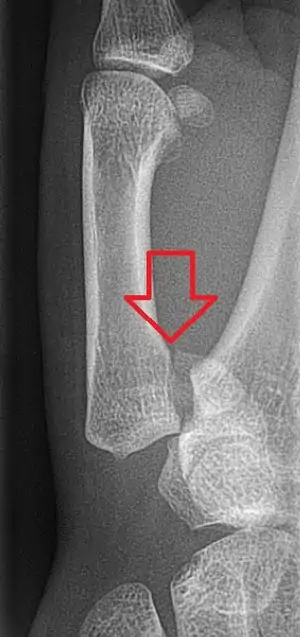

Bennett fracture

A Bennett fracture is a type of broken finger involving the base of the thumb, which extends into the knuckle joint.[4][1] Symptoms generally include thumb swelling and pain.[1] Associated injuries may include ulnar collateral ligament injury of the thumb or trapezium fracture.[1]

The cause is generally a force along the long axis of the thumb.[1] Diagnosis is supported by X-rays.[1] There is nearly always some degree of disruption of the carpometacarpal joint.[2]

The Bennett fracture is an oblique intraarticular metacarpal fracture dislocation, caused by an axial force directed against the partially flexed metacarpal. This type of compression along the metacarpal bone is often sustained when a person punches a hard object, such as the skull or tibia of an opponent, or a wall. It can also occur as a result of a fall onto the thumb. This is a common injury sustained from bike falls, as the thumb is generally extended while around the handle bars. It is also a common injury in car crashes, especially into fixed objects, from the driver holding the steering wheel during impact. The hand moves forward, while the steering wheel rim hyperextends the thumb. Some authors have recently made an assertion against popular belief that the APL tendon is not a deforming force on the Bennett fracture.[6]